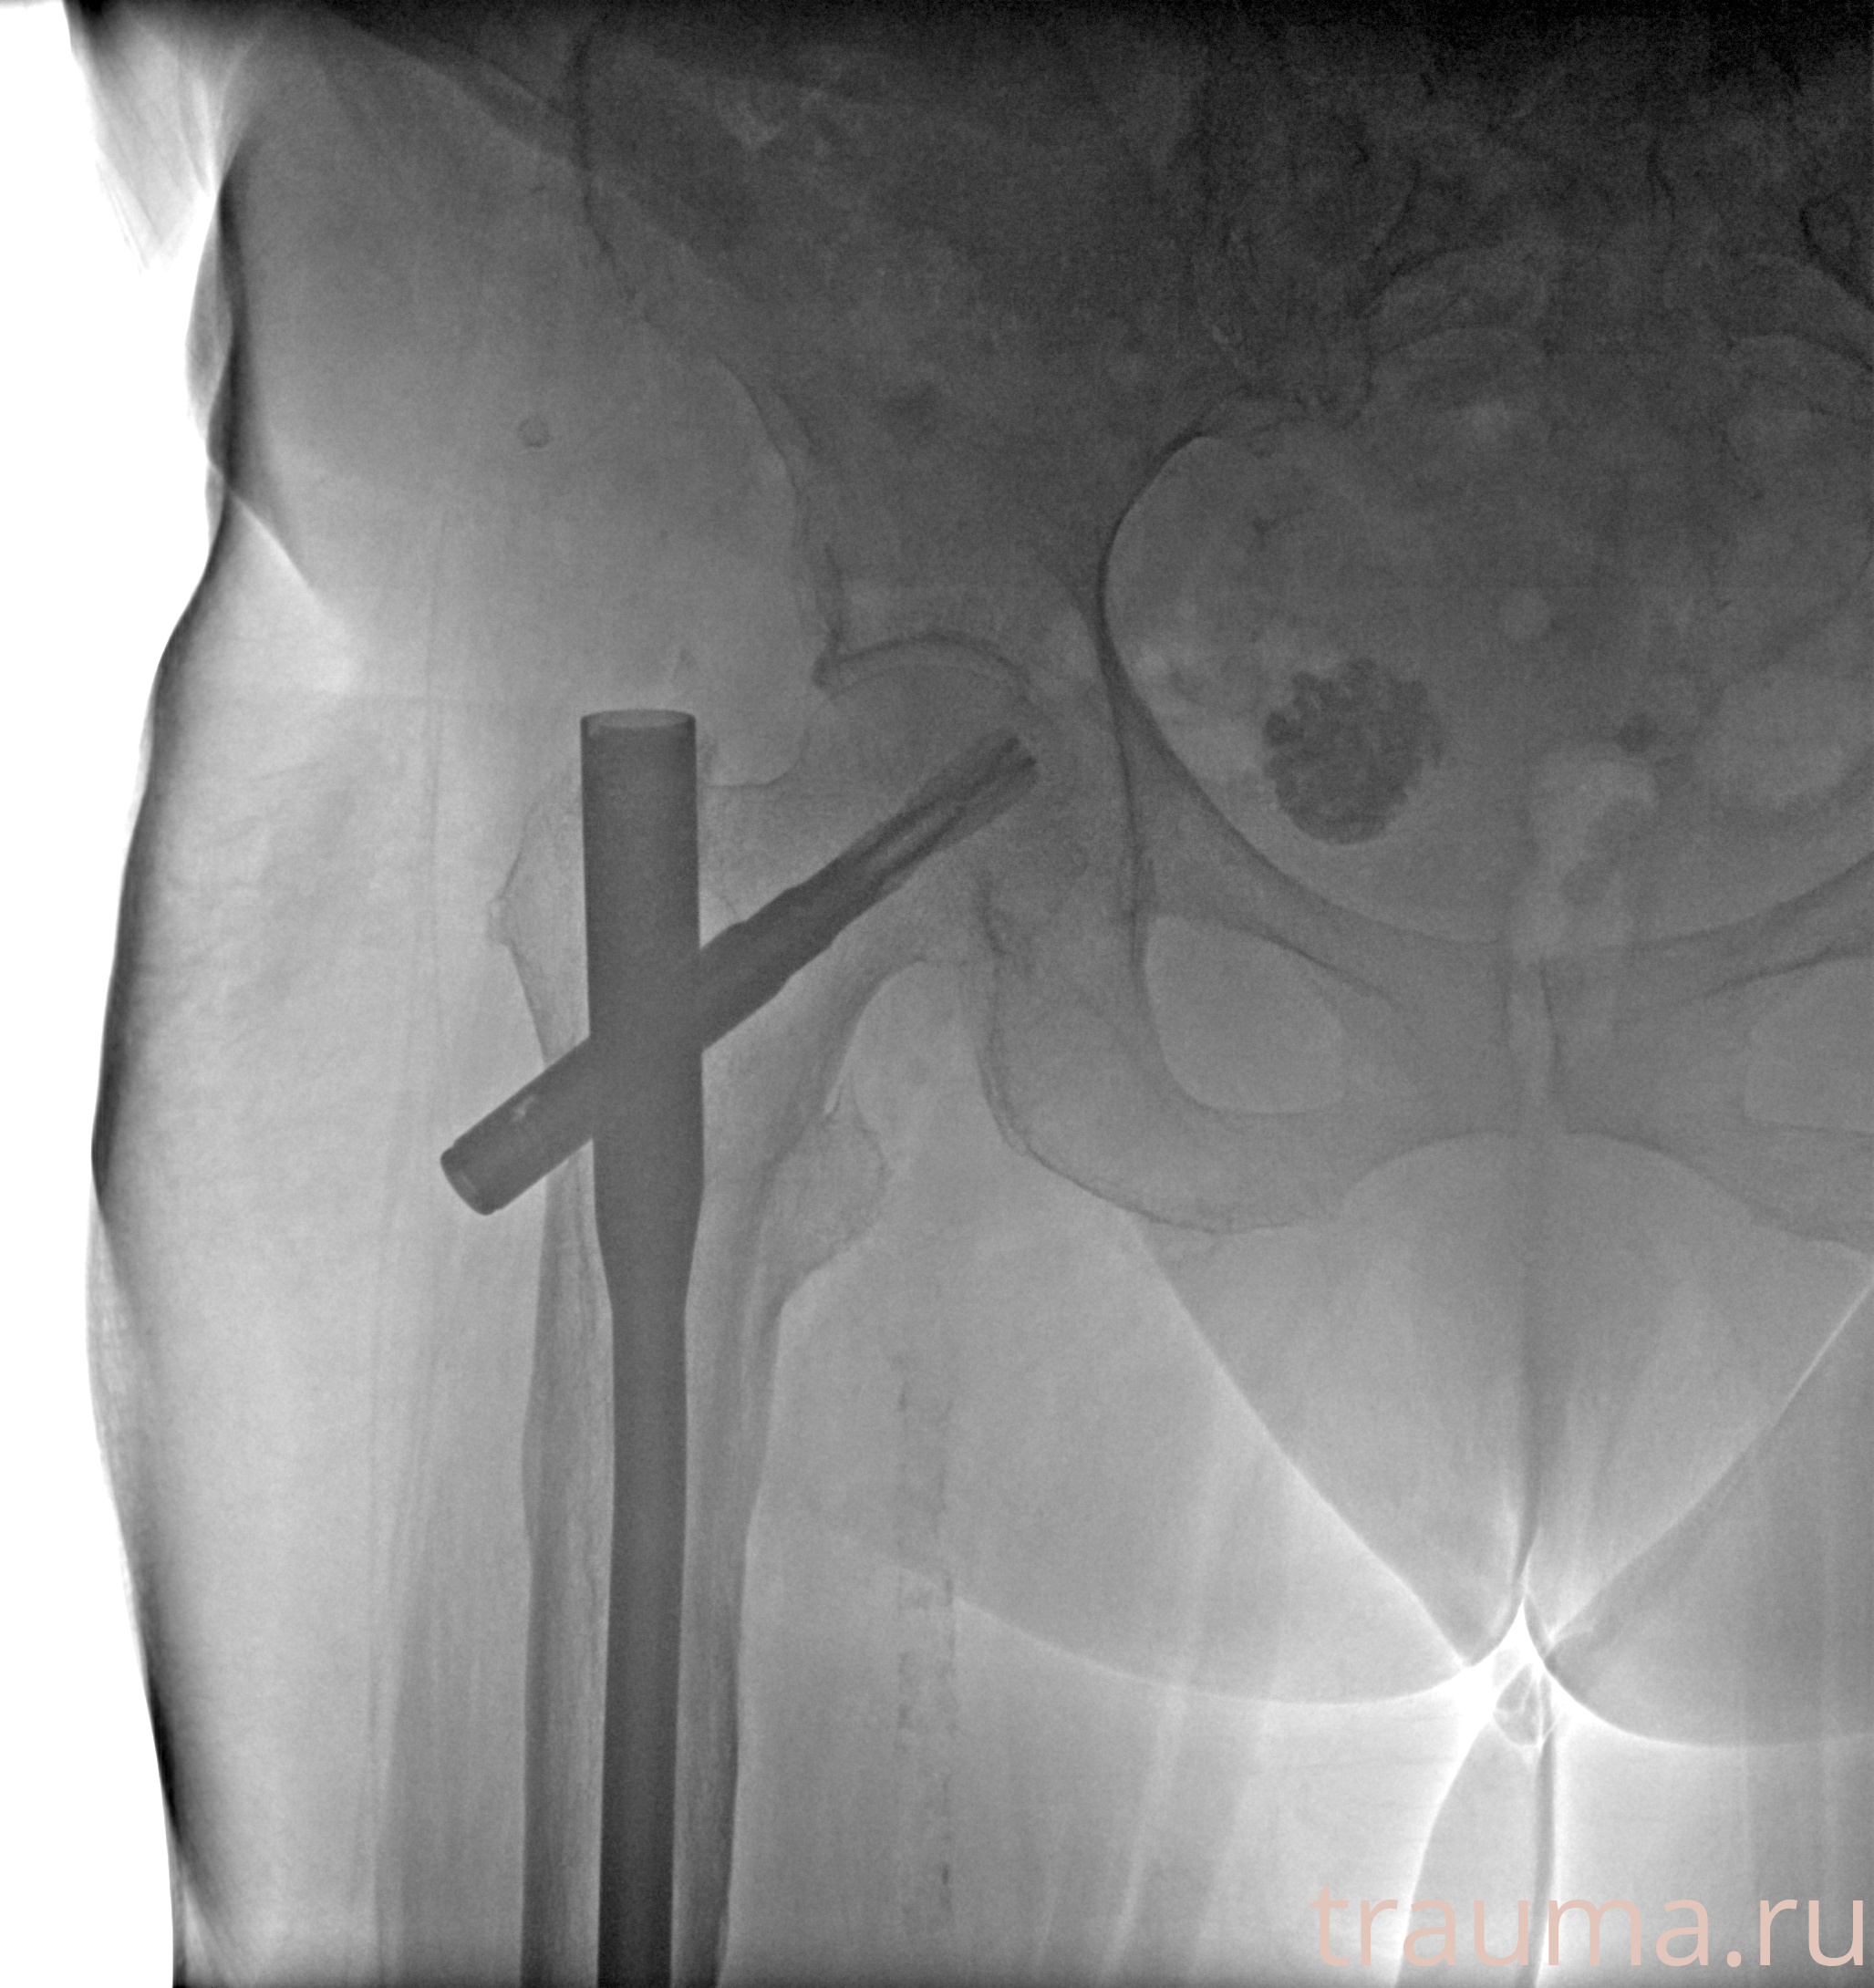

Рентгенограммы